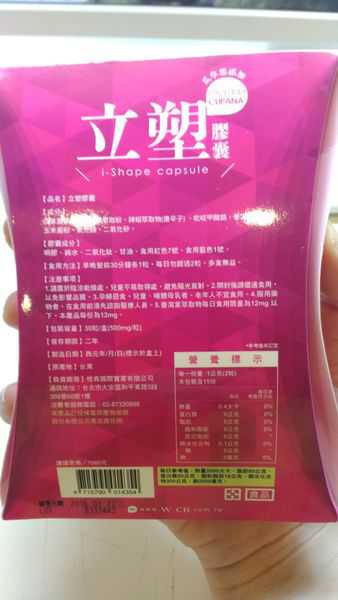

Supercut塑魔纖立塑膠囊的成分有:瓜拿那萃取粉、肉桂萃取粉、辣椒萃取物(唐辛子)、吡啶甲酸鉻、番瀉葉粉末、玉米澱粉、氧化鎂、二氧化矽。

之前上過相關課程,成分表是依照每項成分的多寡來排列順序,排在最前面的就是產品的主要成分!

食用方式:早晚餐前30分鐘各1粒,每日不超過2粒。(多食無益)

番瀉葉萃取物每日食用限量為12mg以下,

番瀉葉萃取物每日食用限量為12mg以下,